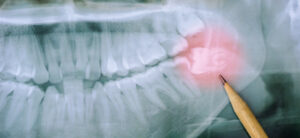

Blöder du ofta från tandköttet men vet inte vad det beror på? Det kan kännas obehagligt och skapa oro. Vi ger dig därför en lista på vad som kan orsaka det – och goda råd för framtiden. Har du ett tandkött som ofta blöder? Uppkommer även smärta eller svullnad om du borstar tänderna för hårt? […]